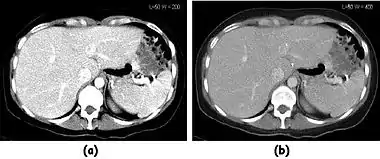

- Reconstructed images can be presented on a computer screen using a grey scale. The grey scale can be chosen to encompass all or some part of the entire range of CT-numbers by selecting a suitable window level and window width. The window width is the range of CT-numbers selected for display and the window level is generally the central CT-number about which the window is chosen. Typically, the highest number is assigned to white and the lowest number to black with all intervening numbers assigned intensities on a linear scale. Air can therefore be displayed as black with cortical bone appearing relatively bright.

![]() Fig. 7.15.2: Effect of window width and level on CT image display: (a) Level = 50; Width = 200. (b) Level = 50; Width = 400. The image in (a) is displayed with greater contrast and appears noisier than that in (b). | ![]() Fig. 7.15.3: Effect of window width and level: (a) Level = -600; Width = 1700. (b) Level = -60; Width = 400. Image (a) displays the lung tissue more clearly, while image (b) can be used to highlight any pulmonary lesions. |

- Examples of image display manipulation are shown in the two figures above. In Figure 7.15.2, the same image of a slice through a patient's liver is displayed using a relatively narrow window (high contrast) and also with a wide window. The image with the narrower window appears noisier, but this is merely a reflection of the fact that the gray scale is spread over a narrow range of CT-numbers.